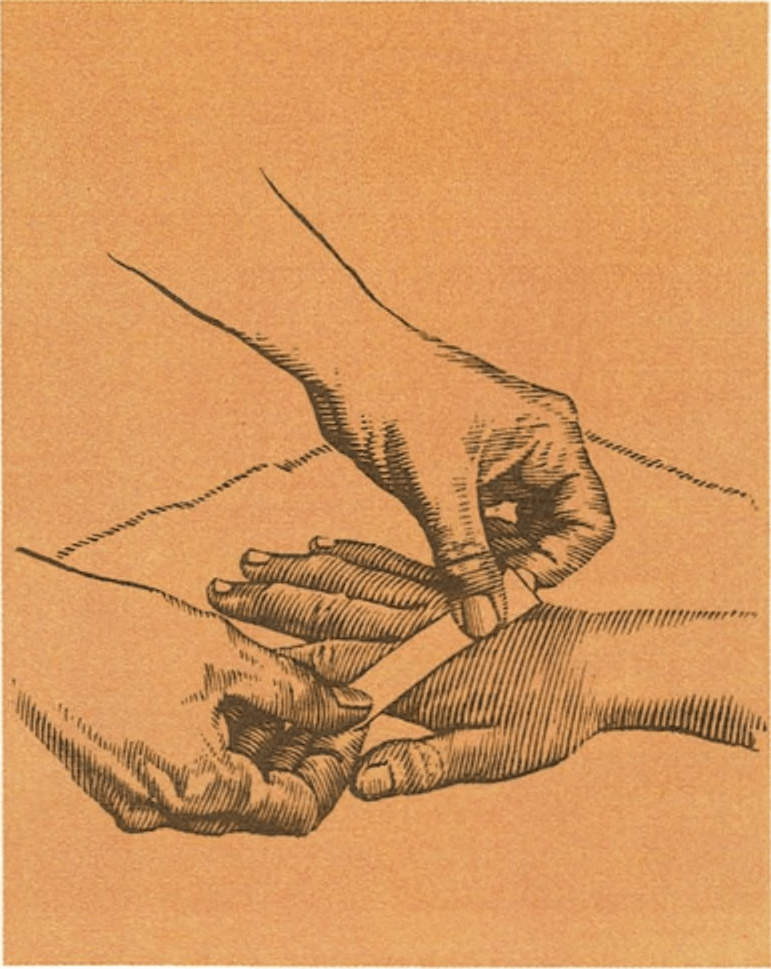

Las heridas en los dedos, la palma de la mano o la muñeca, pueden lesionar algún nervio o tendón. Para averiguarlo se obligará al niño a cerrar los dedos y formar un puño y en el caso de que se haya lesionado un nervio o tendón, no podrá hacerlo. Entonces se llevará al niño al servicio de urgencias de un hospital.